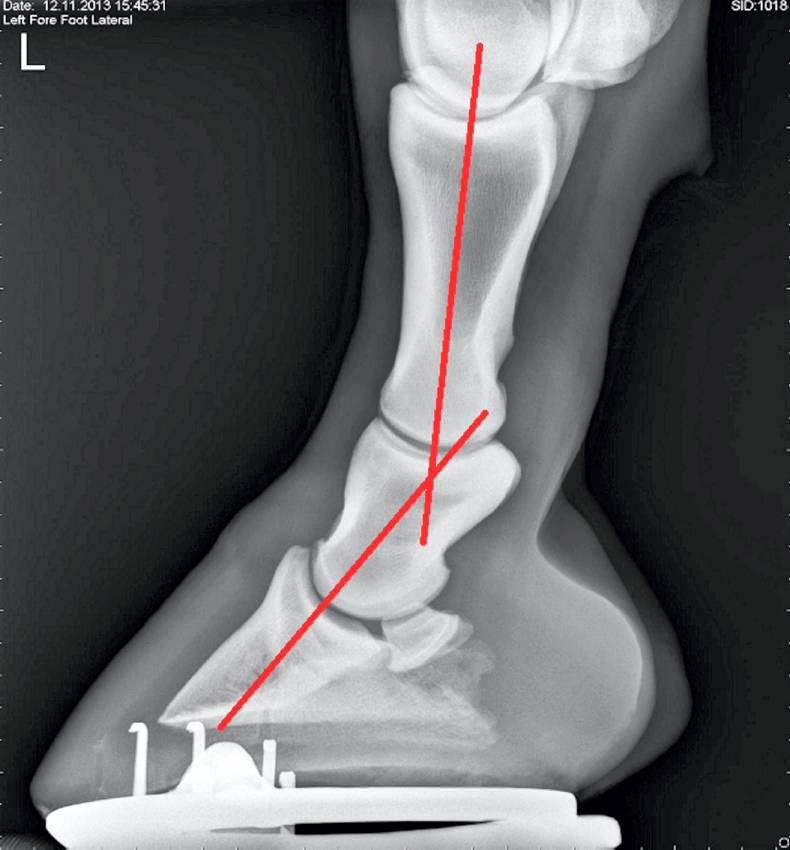

From www.theirishfield.ie

FARRIERY Hoofpastern axis and foot balance Equine Foot Balance X Rays From baseline images to diagnosing complex cases, here’s why x rays should be key components of your horse’s hoof care plan. Radiographic examination of the equine foot can provide the veterinarian and farrier with a wealth of information. Positioning and selection of exposure factors are of central importance if one. Current radiographic techniques applied to the equine foot allow more. Equine Foot Balance X Rays.

From www.researchgate.net

(PDF) The role of radiography in equine foot balance Equine Foot Balance X Rays From baseline images to diagnosing complex cases, here’s why x rays should be key components of your horse’s hoof care plan. A balanced foot is functionally efficient and capable of accommodating the basic purposes of the foot; Current radiographic techniques applied to the equine foot allow more accurate diagnoses and reduce radiation exposure. Radiographic examination of the equine foot can. Equine Foot Balance X Rays.